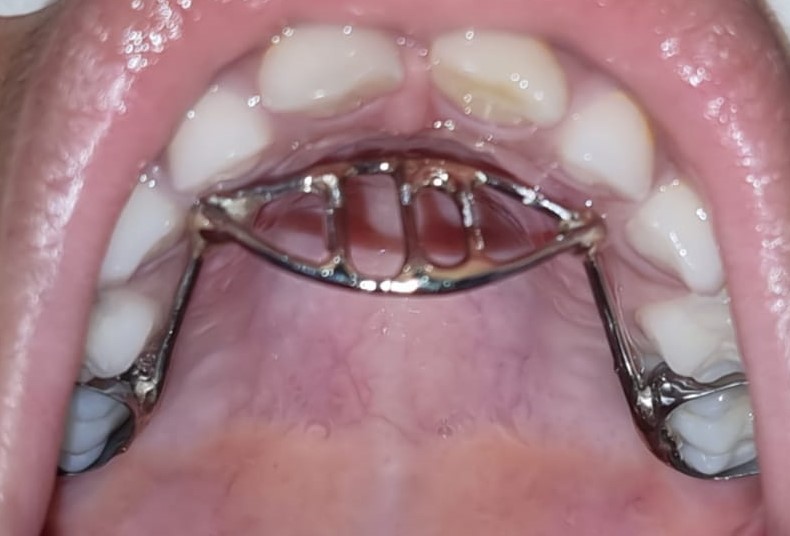

7) Manvir – Tongue Thrusting habit breaking appliance